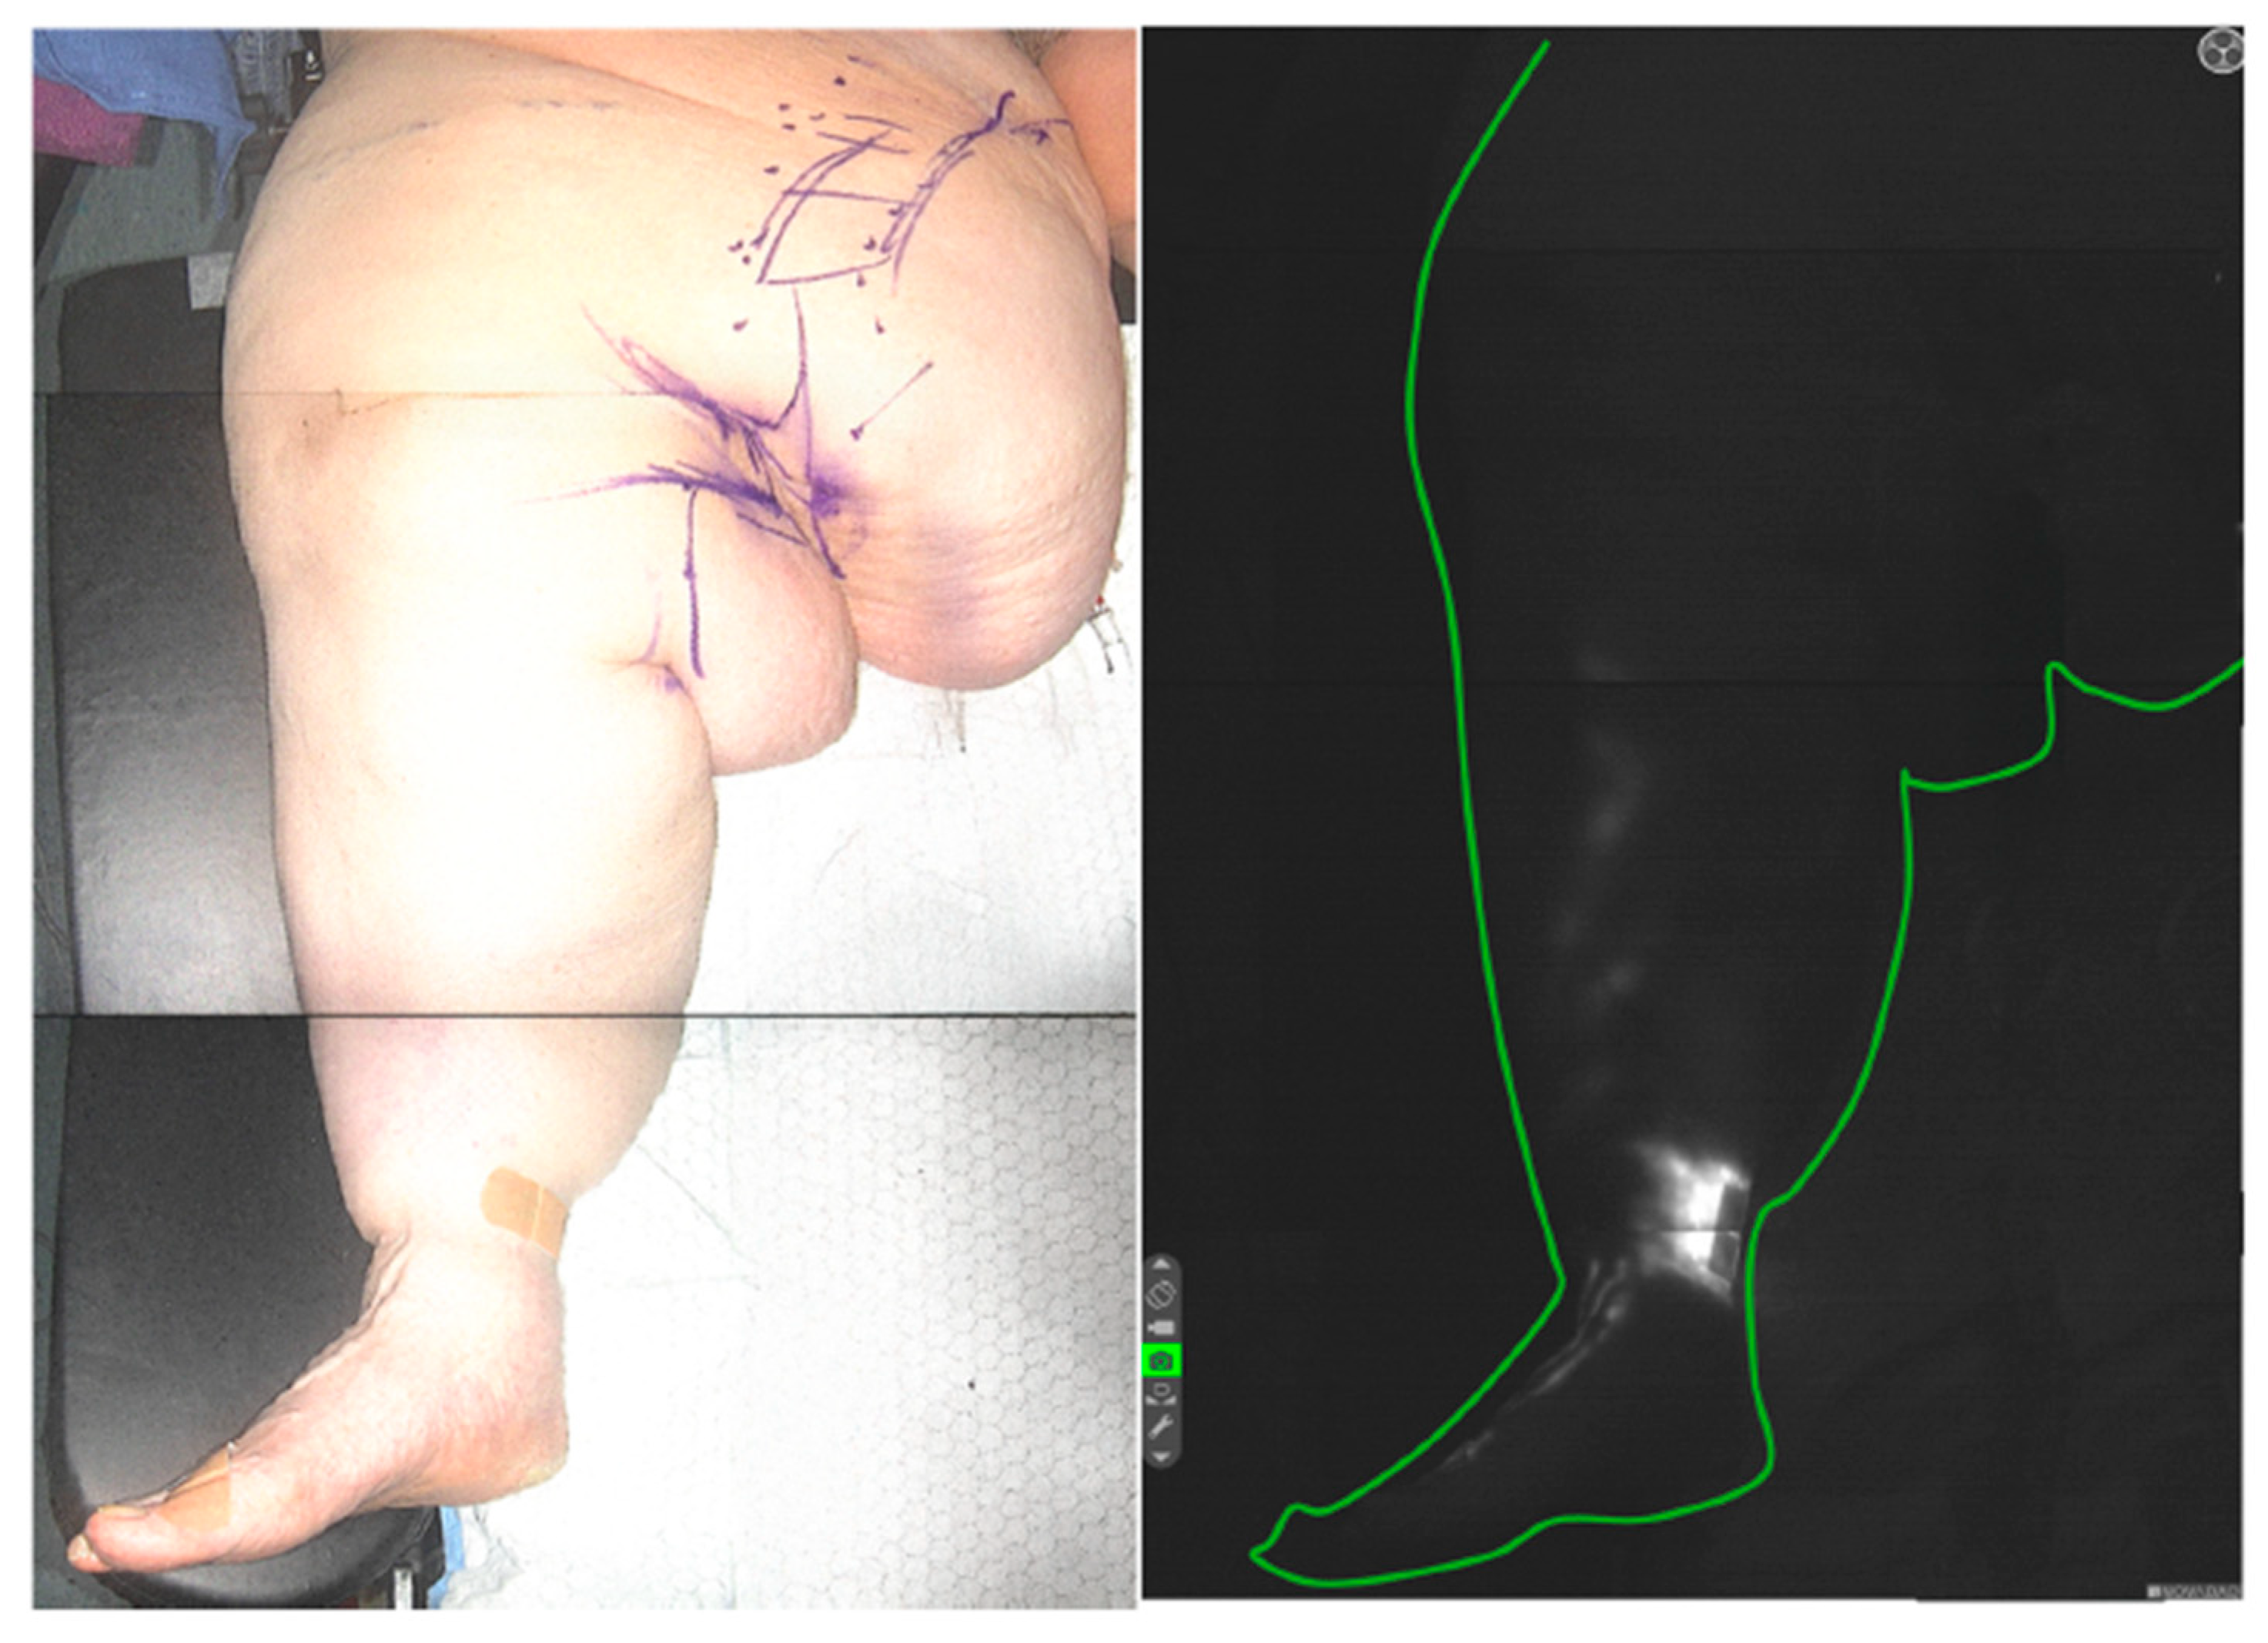

ICG Lymphography

2.2. Procedure